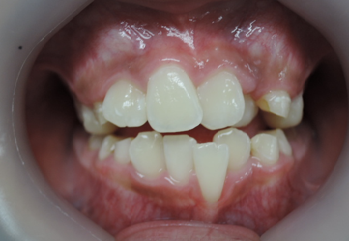

よく診る、難しい症例(奥歯の隙間)